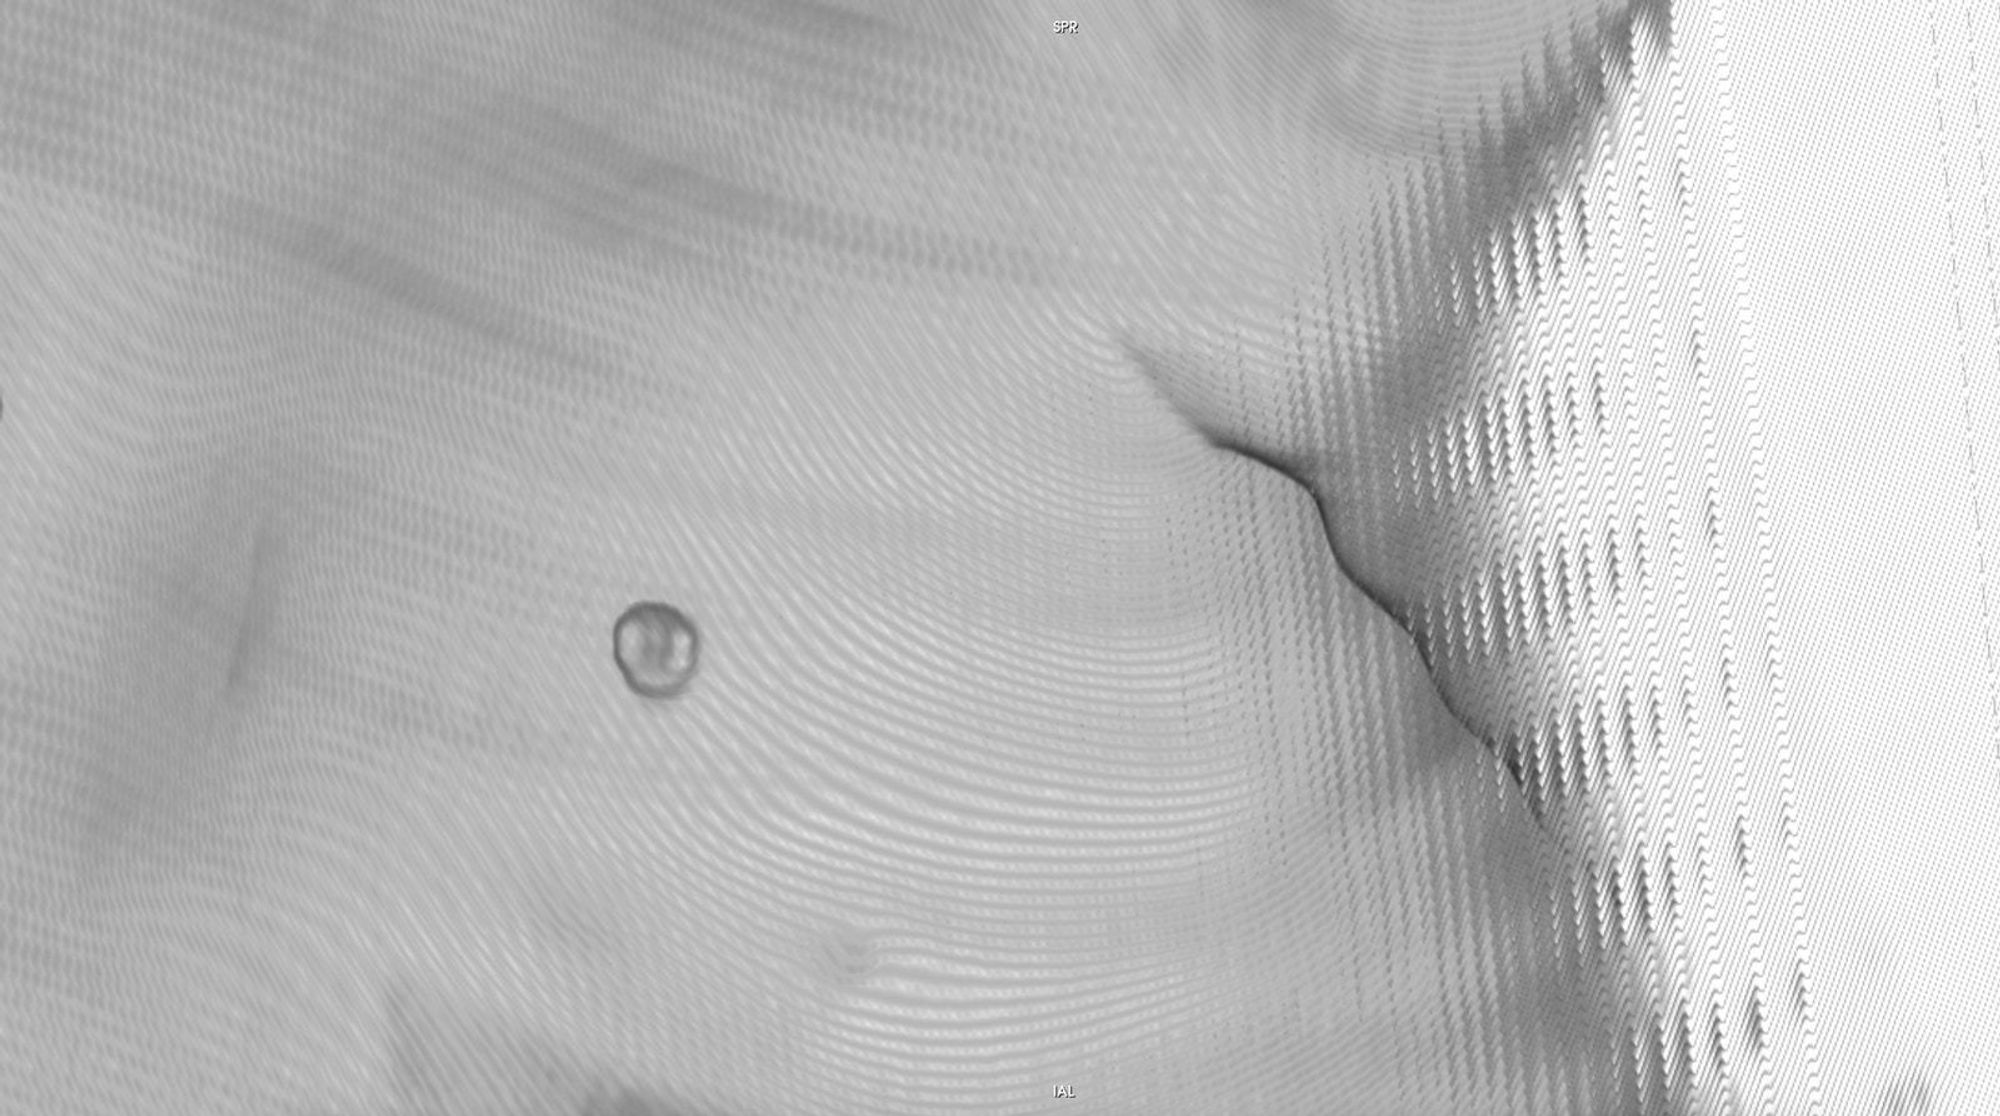

The history of medicine can be understood as an on-going endeavour to comprehensively visibilise the body, to pull it from obscurity, to open it out to vision. ‘The x-ray image, with its simultaneous view of the inside and outside, turned the vantage point of the spectator-subject inside out.’ * With the invention of the x-ray, the surface of the body, and its distinction from the world, was dissolved and lost in the image.

In this project, I look at the visual limit between the inside and the outside, the inner and the outer. I combine different visual approaches to materialise the body, using medical imagery, photography from manuals and radiology software. Decontextualised from their origin, these images speak of medicine’s relationship to both sex and violence, and remind us that, in medicine, to go into the body is always to go into the image first.